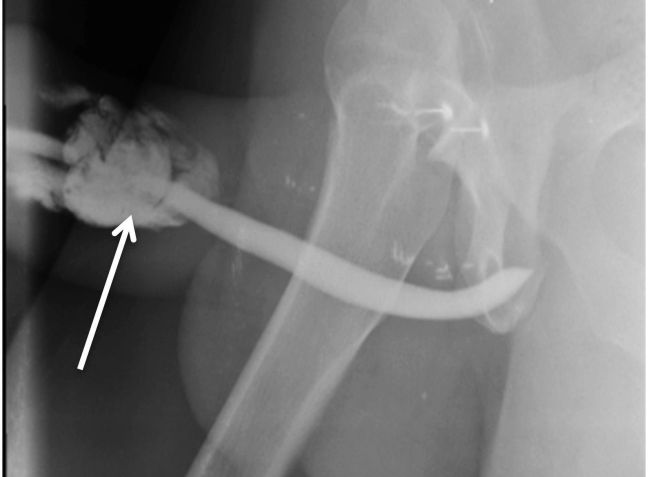

A ultrassonografia peniana mostrou um hematoma no corpo do pênis em corpos cavernosos dos dois lados do órgão, mais acentuadamente no lado esquerdo. Exame de ressonância magnética revelou os três locais da fratura.

O paciente foi conduzido para cirurgia de emergência e reparo da fratura peniana e lesão uretral, que foi realizada por um urologista. Segundo o estudo, não havia nenhum outro local de lesão além daqueles observados na ressonância magnética.